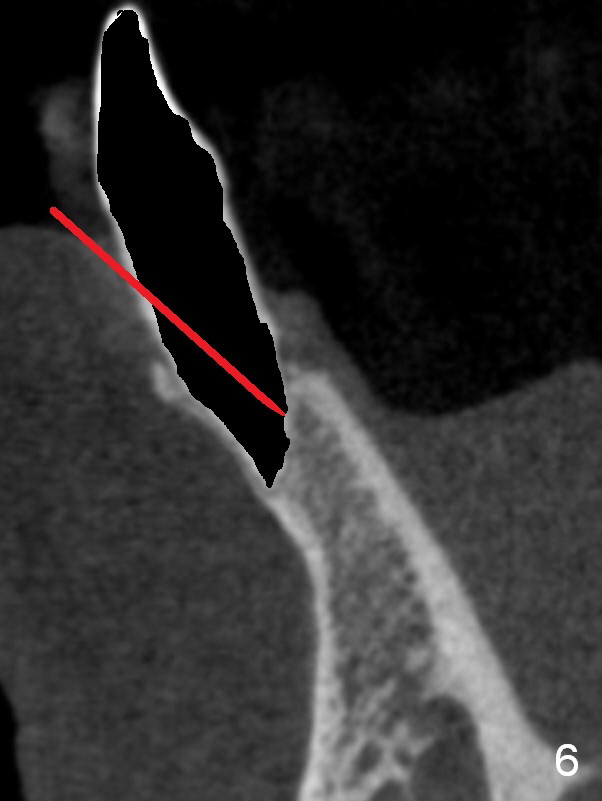

A 74-year-old man has several missing teeth (Fig.1). His 1st goal is to replace the lower left lateral incisor (Fig.2). The residual root has an apical lesion (Fig.3 *). To describe intraop findings, a CT image of a different patient is used (Fig.4 coronal section; B: buccal; L: lingual). After extraction, the buccal plate is found to be thin and low (Fig.5 arrowheads). A 1.5 mm pilot drill (Fig.6 red line) is used to initiate osteotomy in the lingual plate of the socket. Once the drill penetrates the lingual plate, the trajectory changes and the depth is 17 mm from the gingival margin (Fig.7). A PA is taken (Fig.8); it appears that the osteotomy can be extended more apically. When the pilot drill extends to 20 mm, there is sudden empty feeling. The lingual plate has perforated (Fig.9). A new osteotomy is established buccally (Fig.10 pink). To avoid buccal plate perforation, especially in the buccal undercut area (>), the coronal end of the drill has to be tilted buccally (<--). An angled abutment (3x20 mm, 15°) is placed (Fig.11,12). The abutment is modified (Fig.13,14) to accommodate an immediate provisional (Fig.15,16 P). Perio dressing is to be applied to prevent the bone graft from getting dislodged buccally (Fig.15). The dressing is in place 7 days postop (Fig.17).